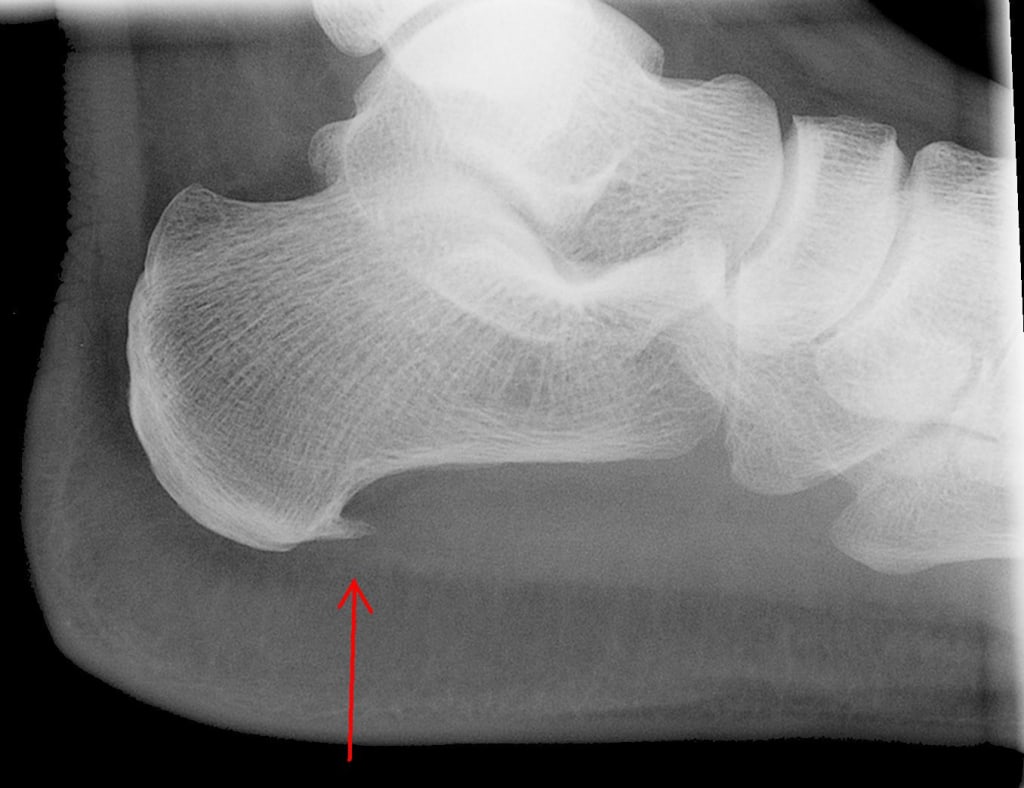

Heel spurs are bony protrusions that develop on the underside of the heel bone.

Heel spurs are bony protrusions that develop on the underside of the heel bone. They often result from the excessive strain and stress placed on the foot's ligaments and muscles over time. Heel spurs can cause intense pain, especially when walking or standing for extended periods. They are commonly associated with conditions like plantar fasciitis, Achilles tendinitis, and excessive pronation.